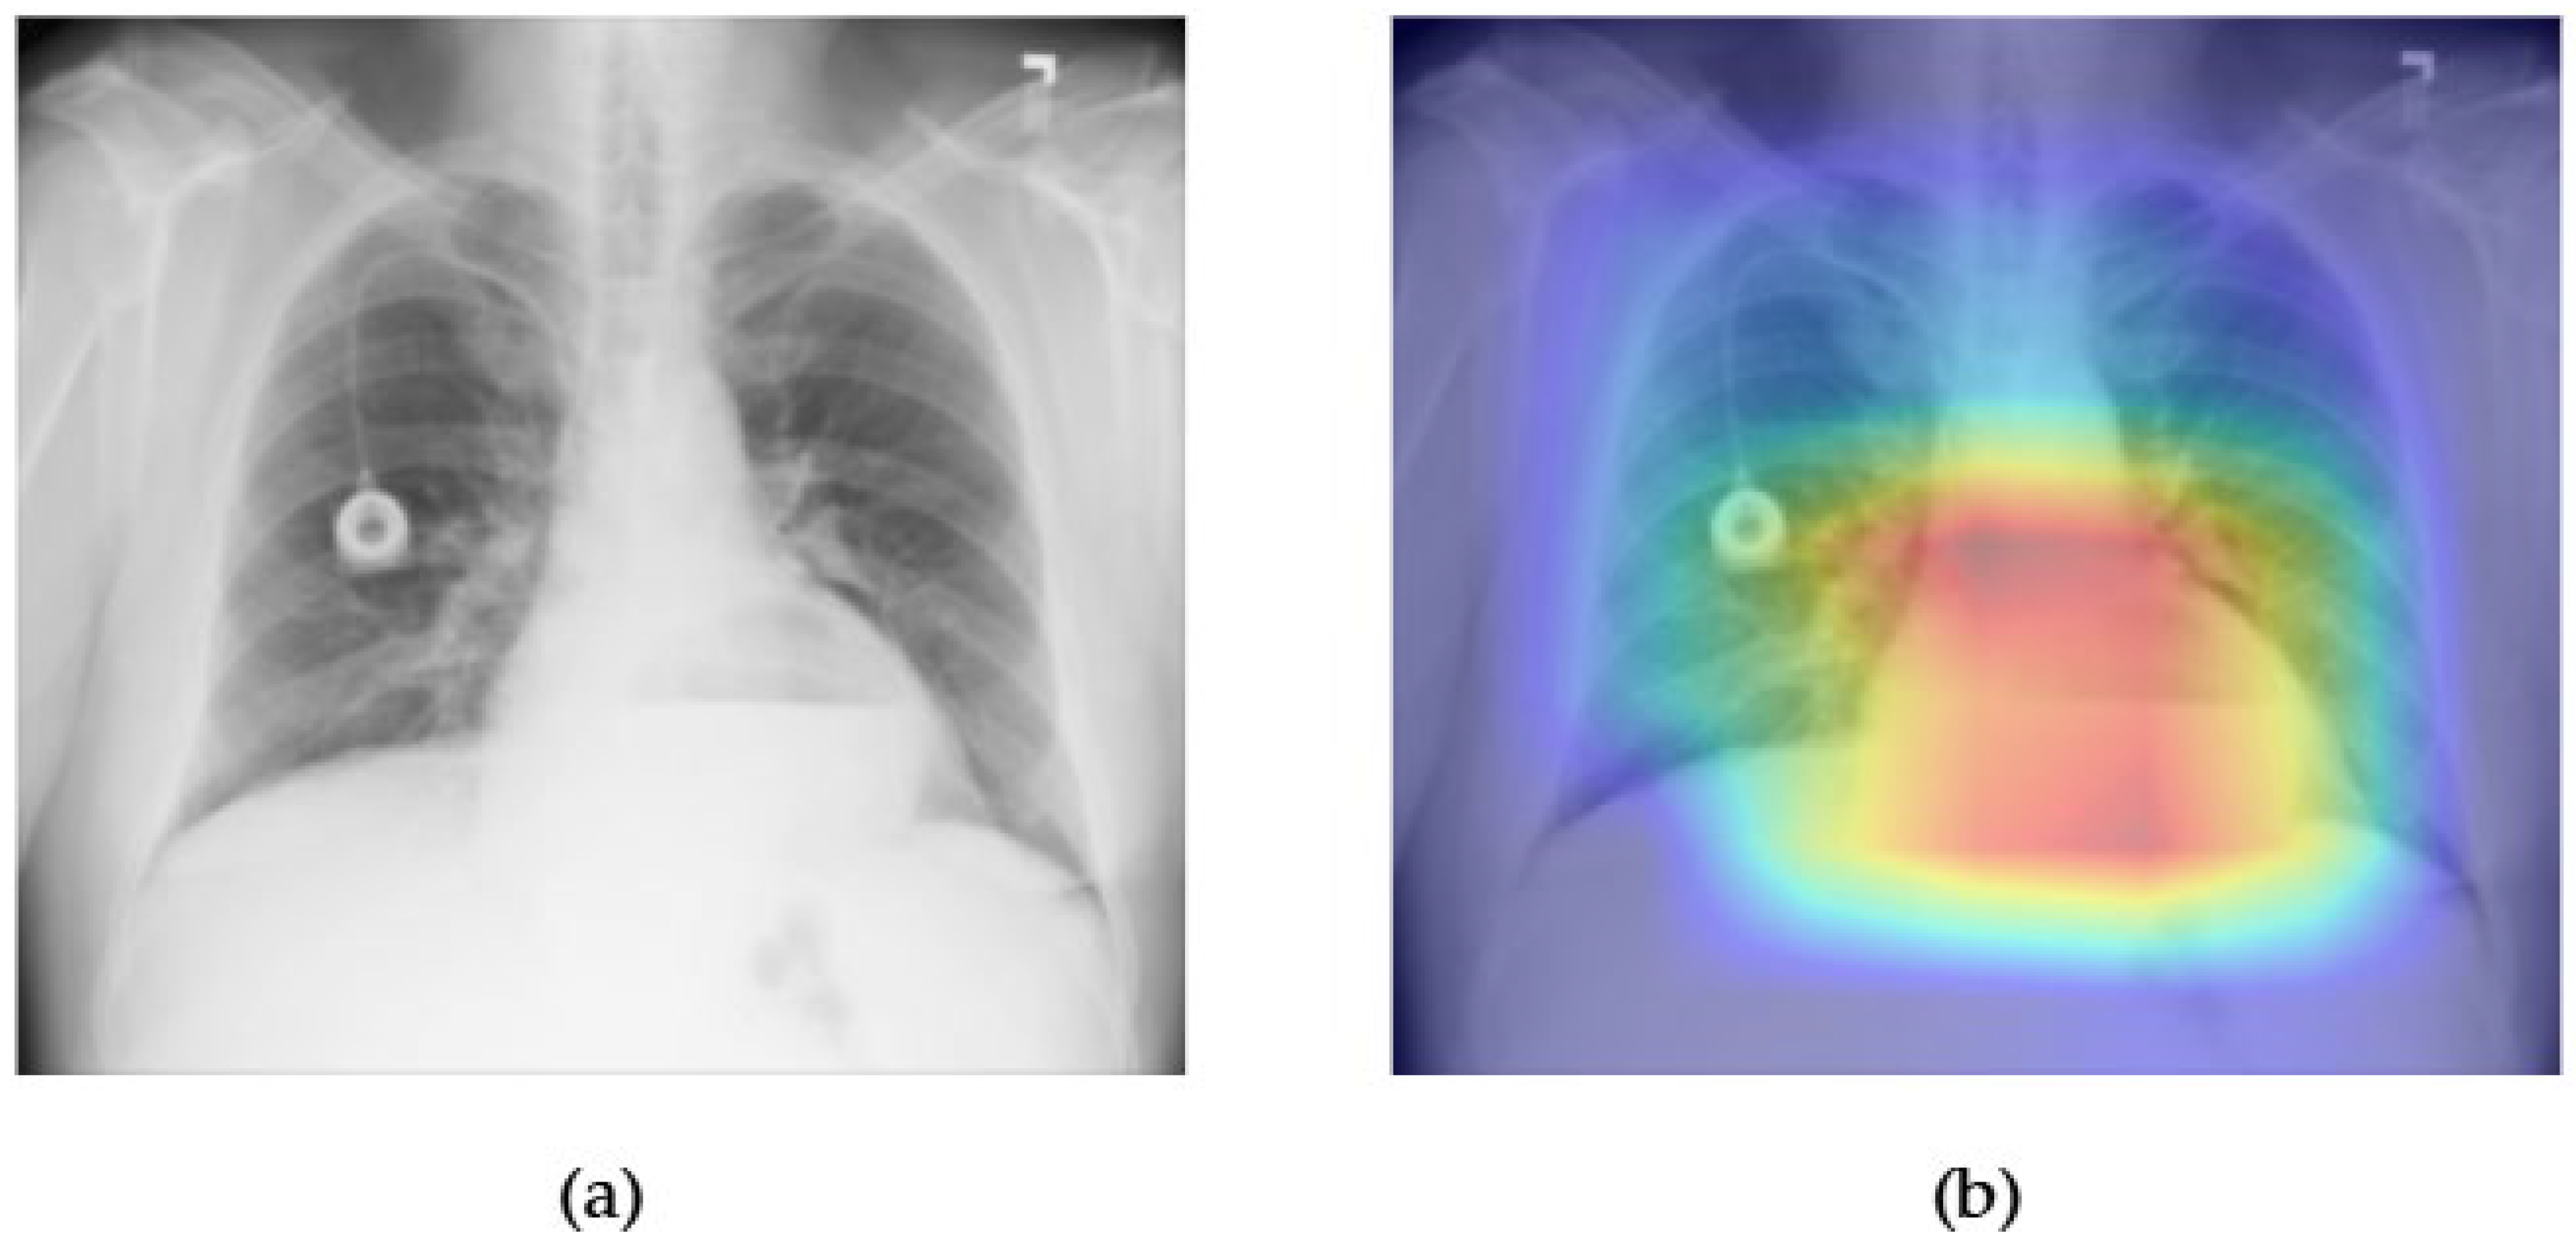

- Although our Grad-CAM-based explainability provides useful localization cues, it is inherently limited by its post hoc nature and reliance on gradient flow from the final convolutional layers. Future research could incorporate advanced interpretability techniques such as Layer-wise Relevance Propagation (LRP), Integrated Gradients, or attention rollouts in Transformers, which may offer a more complete understanding of model reasoning.